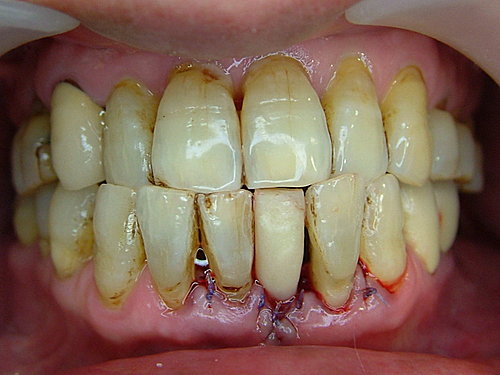

某先生 後牙缺牙 而前牙因牙周病 牙齒動搖 ..... 後牙不作活動假牙 門牙不願修磨兩旁牙齒來做牙橋

所以都選用植牙方式.....

牙結石厚 先洗牙清乾淨再說 .....

下顎門牙因牙周病 骨頭吸收嚴重 牙齒地基流失 ....